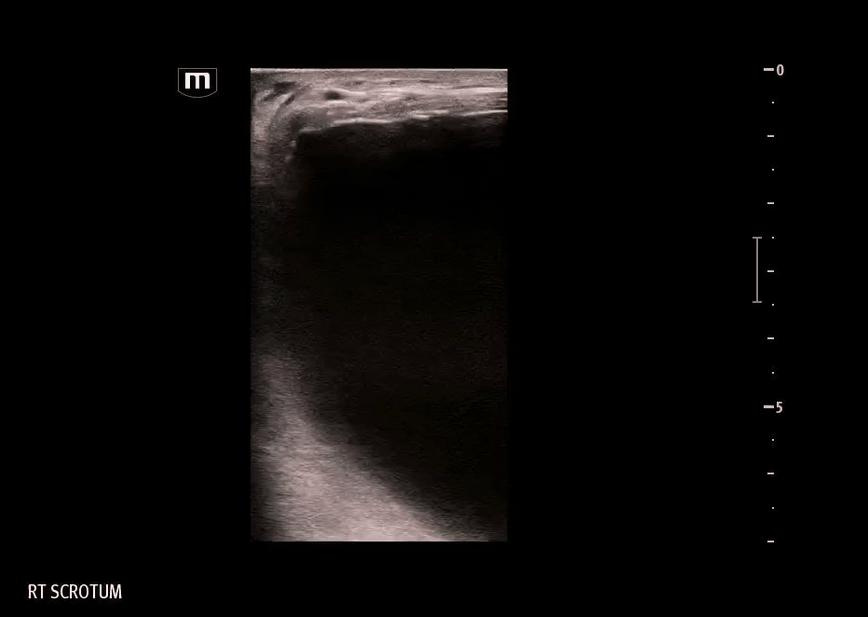

Ultrasound:

Ultrasound was performed on the R scrotum

Findings on our bedside ultrasound:

• The structure is anechoic - fluid-filled, appears to be simple fluid

• The structure has no peristalsis, and there is a lack of typical bowel wall findings - probably not bowel or inguinal hernia

• The structure does not seem to be within the tunica vaginalis - not a hydrocele, where the simple fluid collection would be seen surrounding the testicle itself

In comparison, our image didn’t show typical bowel wall appearance but the swelling/mass was located within the scrotum, so what did the hernia contain?